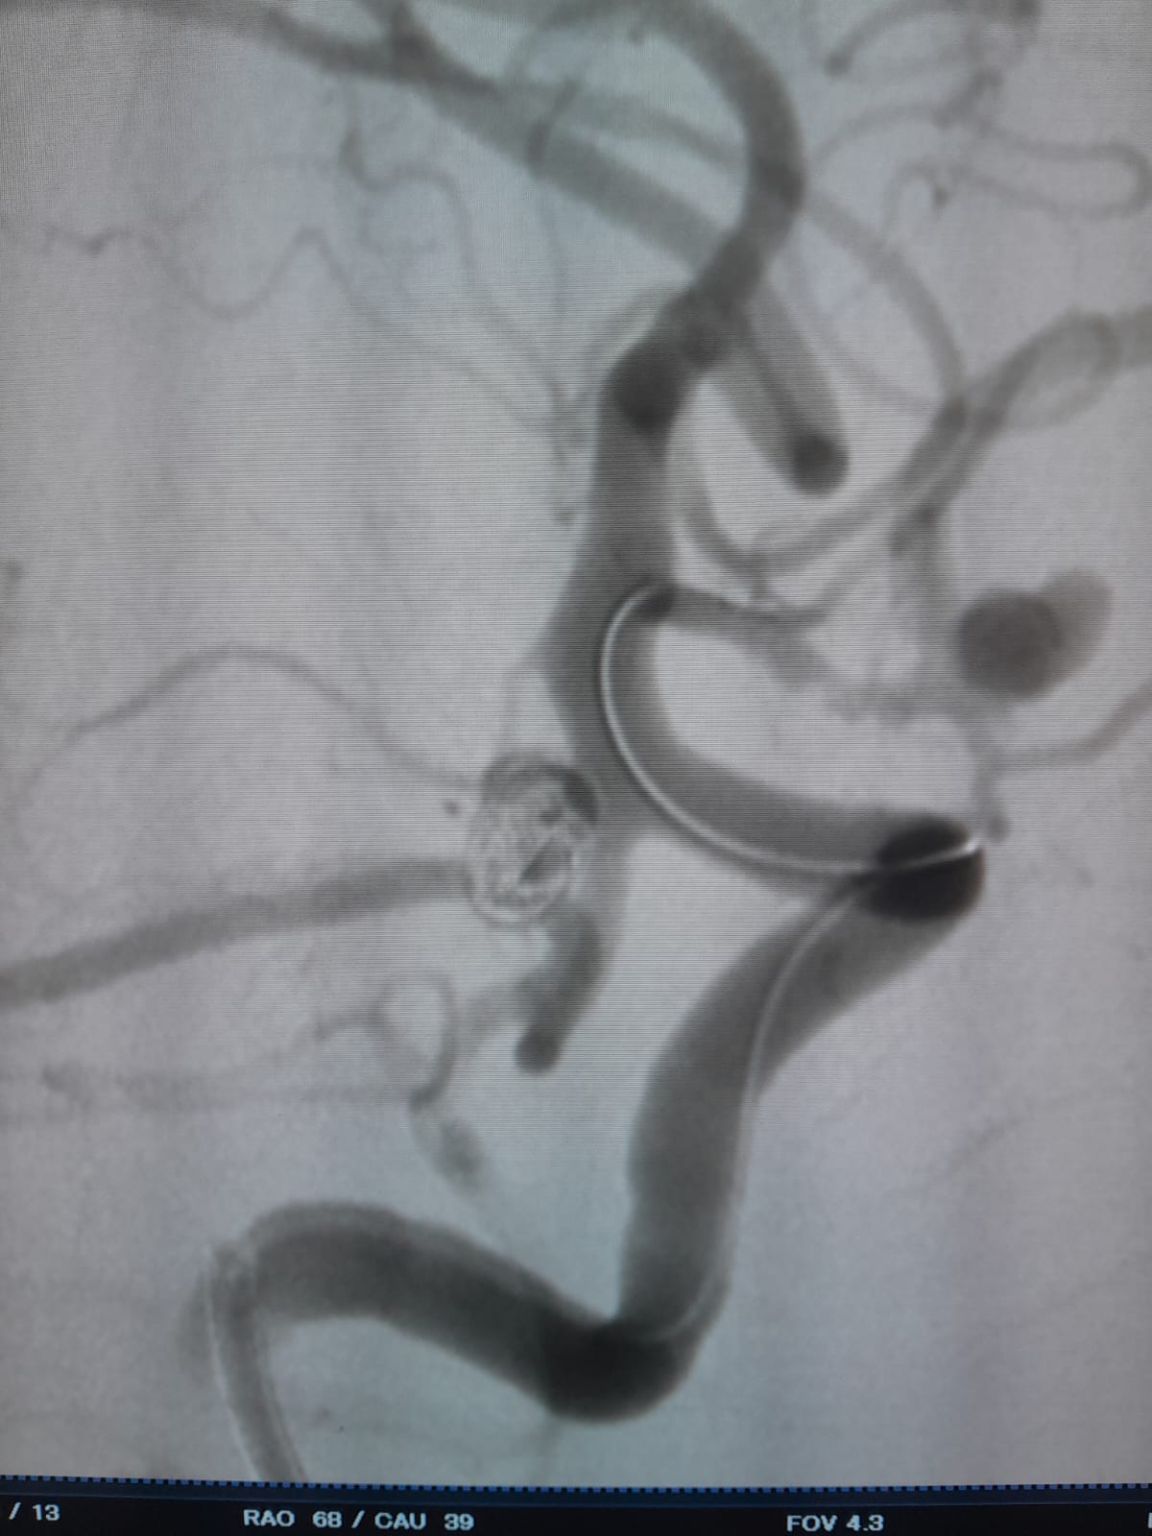

Aneurisma Comunicando Artéria Posterior (Re-tratamento)

Durante o acompanhamento, observou-se enchimento residual no aneurisma da artéria comunicante posterior previamente tratado. A equipe acessou novamente o site usando o Frepass®Microcateter descartável (TJMC18 Plus) e implantado com sucesso um Nuva®Desvio do fluxo (TJED-D-4.5-16), que demonstrou a aposição ideal da parede e o desvio excelente do fluxo, conduzindo aos resultados altamente satisfatórios do tratamento.